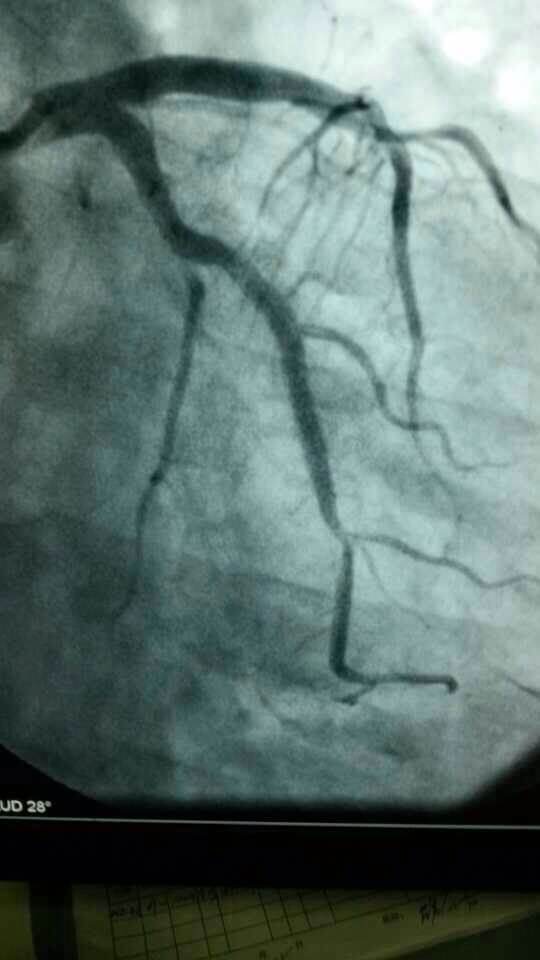

心内科8个小时成功抢救3名心梗患者

心内科医务人员在崔勇主任的带领下,蔡亚滨、林福根、雷建林、陈明辉、何晓、李仲伟等抢救团队连续奋战 8个小时成功抢救3名心梗患者。虽然工作艰辛,但接诊的三位病人都能转危为安,对医生来讲是最大的安慰。

专家提示:我国心血管病的发病率和死亡率常年居高不下,还出现明显年轻化趋势,白领、公务员等群体英年猝死的新闻屡见不鲜。在已经救治的近200例胸痛患者中,80%以上是急性冠状动脉综合征(这其中包含了心梗、不稳定心绞痛等)这类急性危险的病症,专家建议,40岁以上的人群,胸闷、胸痛突然发作,尤其是劳累后发作,或者一会儿痛一会儿不痛的要及时就诊。